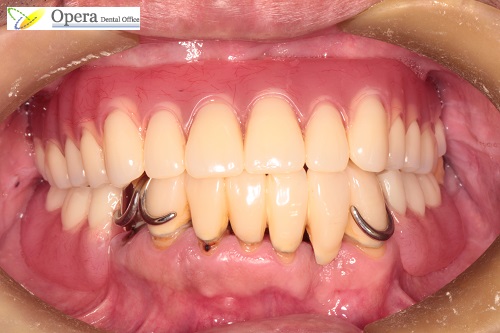

初診時です。

上の残っている2本の歯は歯周病で残すことは不可能です。

下の歯に関しては、歯並びが前後的に崩れていたため、この歯並びに合わせて上の入れ歯を装着すると、入れ歯がガタついて落ちてきてしまいます。

完成したところです。

この金属部分がインプラントです。インプラントにレジリエンツテレスコープを取り付けています。

金色の金属部分がインプラントにはまります。

横から見た歯並びも整っていると思います。